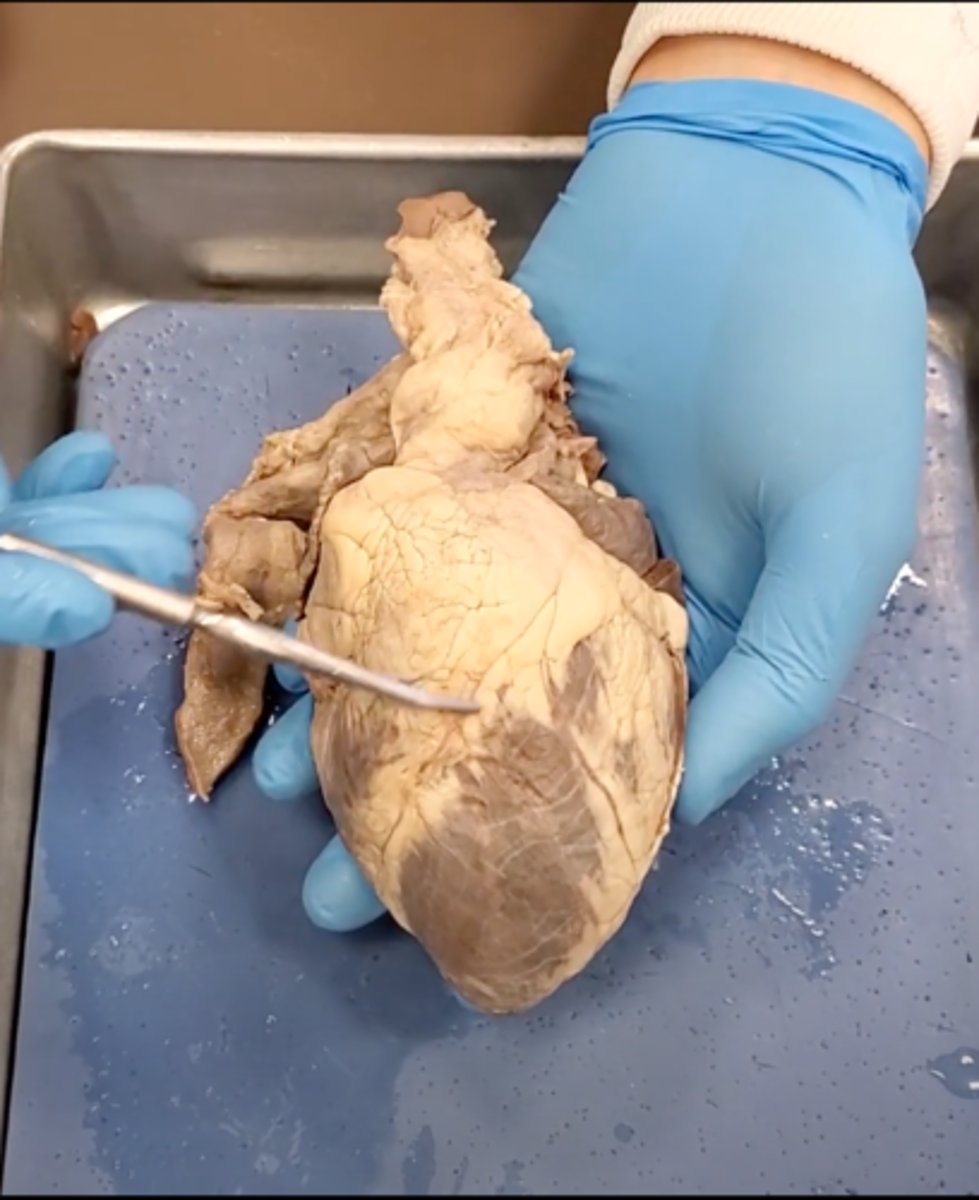

yellow sash of fat that tells you this if the front side of the heart (dissection)

pulmonary trunk (dissection)

t-shaped ribbon of fat on back side of heart (dissection)

left auricle (dissection)

right auricle (dissection)

left ventricle (dissection)

right ventricle (dissection)

right atrium (dissection)

left atrium (dissection)

bicuspid valve (dissection)

tricuspid valve (dissection)

aortic semilunar valve (dissection)

located between the left ventricle and the aorta

chordae tendineae (dissection)

thin bands of fibrous tissue that attach to the valves in the heart and prevent them from inverting